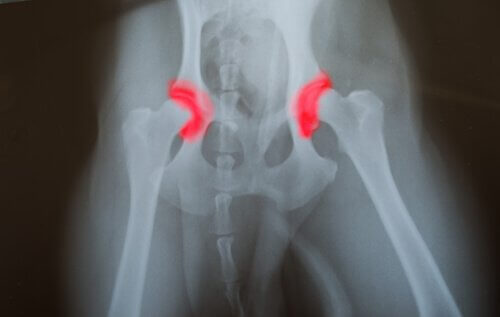

Kalça veya dirsek displazisi kuşaktan kuşağa geçen kalıtsal bir hastalıktır. Eklemi oluşturan kemiklerin- ya kalça ya da dirsekte olur – doğru yerleştirilmemiş ya da hizalanmamış olmasından kaynaklanır. Bu onların birbirlerine sürtmelerine ve uygunsuz hareketler yapmalarına neden olur. Bu, eklemlerin arızalanmasına neden olan diğer sorunlara yol açan daha hızlı bir aşınmaya neden olur. Bu hastalıkla ilgili sorun sessiz bir hastalık olmasıdır.

Bu, problemin doğumdan beri bile uzun süredir var olabileceği anlamına gelir, ancak hayvan yaşamın sonraki aşamalarına kadar herhangi bir acı hissetmeyecektir. Bunu fark edeceksiniz çünkü evcil hayvanınız yemek yemekten ve zıplamaktan neredeyse hiç hareket edememeye kadar kötüleşecektir.

Genetik yapıları nedeniyle bu hastalığa yakalanma olasılığı daha yüksek olan bazı ırklar vardır. Bunlar çoğunlukla büyük köpeklerdir, çünkü eklemleri çok fazla ağırlık taşımak zorundadır. Ayrıca, bu tıbbi durum, hızlı bir şekilde büyüyen köpekleri etkiler, çünkü eklemlerini güçlendirmek için zamanları yoktur.